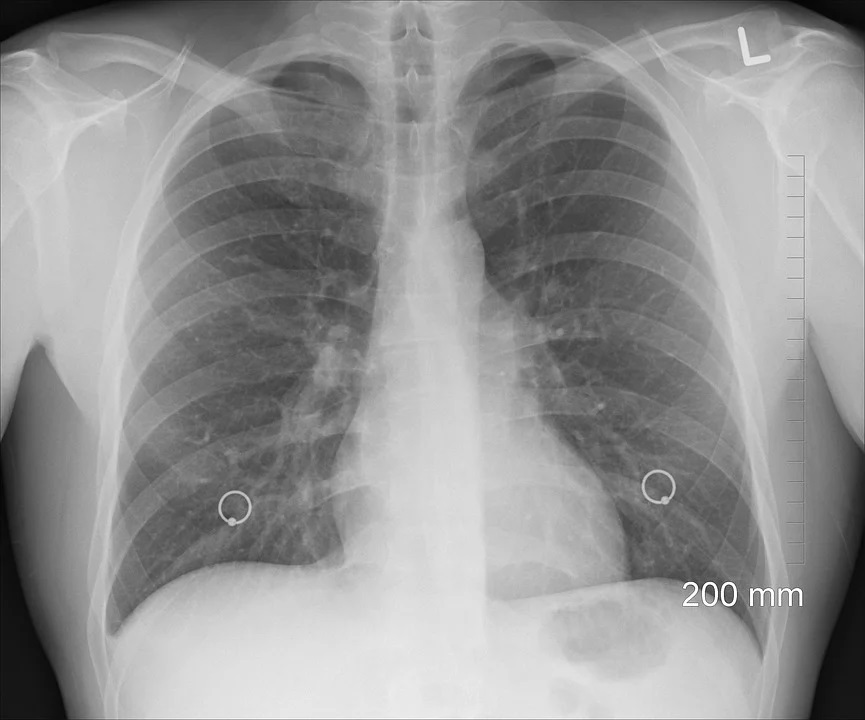

Díky útlumu těžkého průmyslu v posledním desetiletí už neplatí Ostravsko za region s nejčastějším výskytem zhoubných nádorů plic. Foto: Pixabay